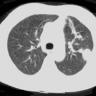

Patients with recurrent or persistent spontaneous pneumothorax are treated thoracoscopically. Those with blebs or small bullae are generally managed by stapler resection of the lesions. We have recently experimented with a new device (Endo-Floating Ball) for the coagulation of blebs as an alternative to endostapler resection.